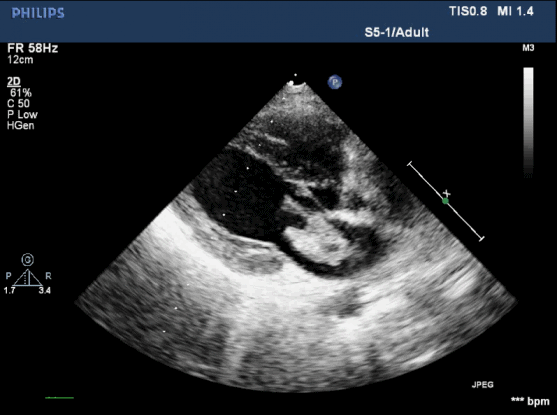

新华医院心胸外科张丽医师立即给她查了心脏超声,发现左侧心房里有一个3.5cm左右的不规则包块,分成多叶,随着血流而飘舞,并且舒张期堵住二尖瓣的入口,高度怀疑心房粘液瘤。这个包块表面还有很多小的凸起,像葡萄串一样,随时可能脱落,还会进一步导致脑梗或腹腔脏器等梗塞,造成器官坏死。如果整个包块脱落,那么可能直接导致患者死亡,病情十分危险。

心脏超声检查图像